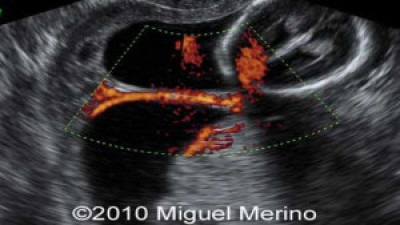

Ultrasonografías Varias

Envíado por Dr. Miguel Ángel Merino Araujo